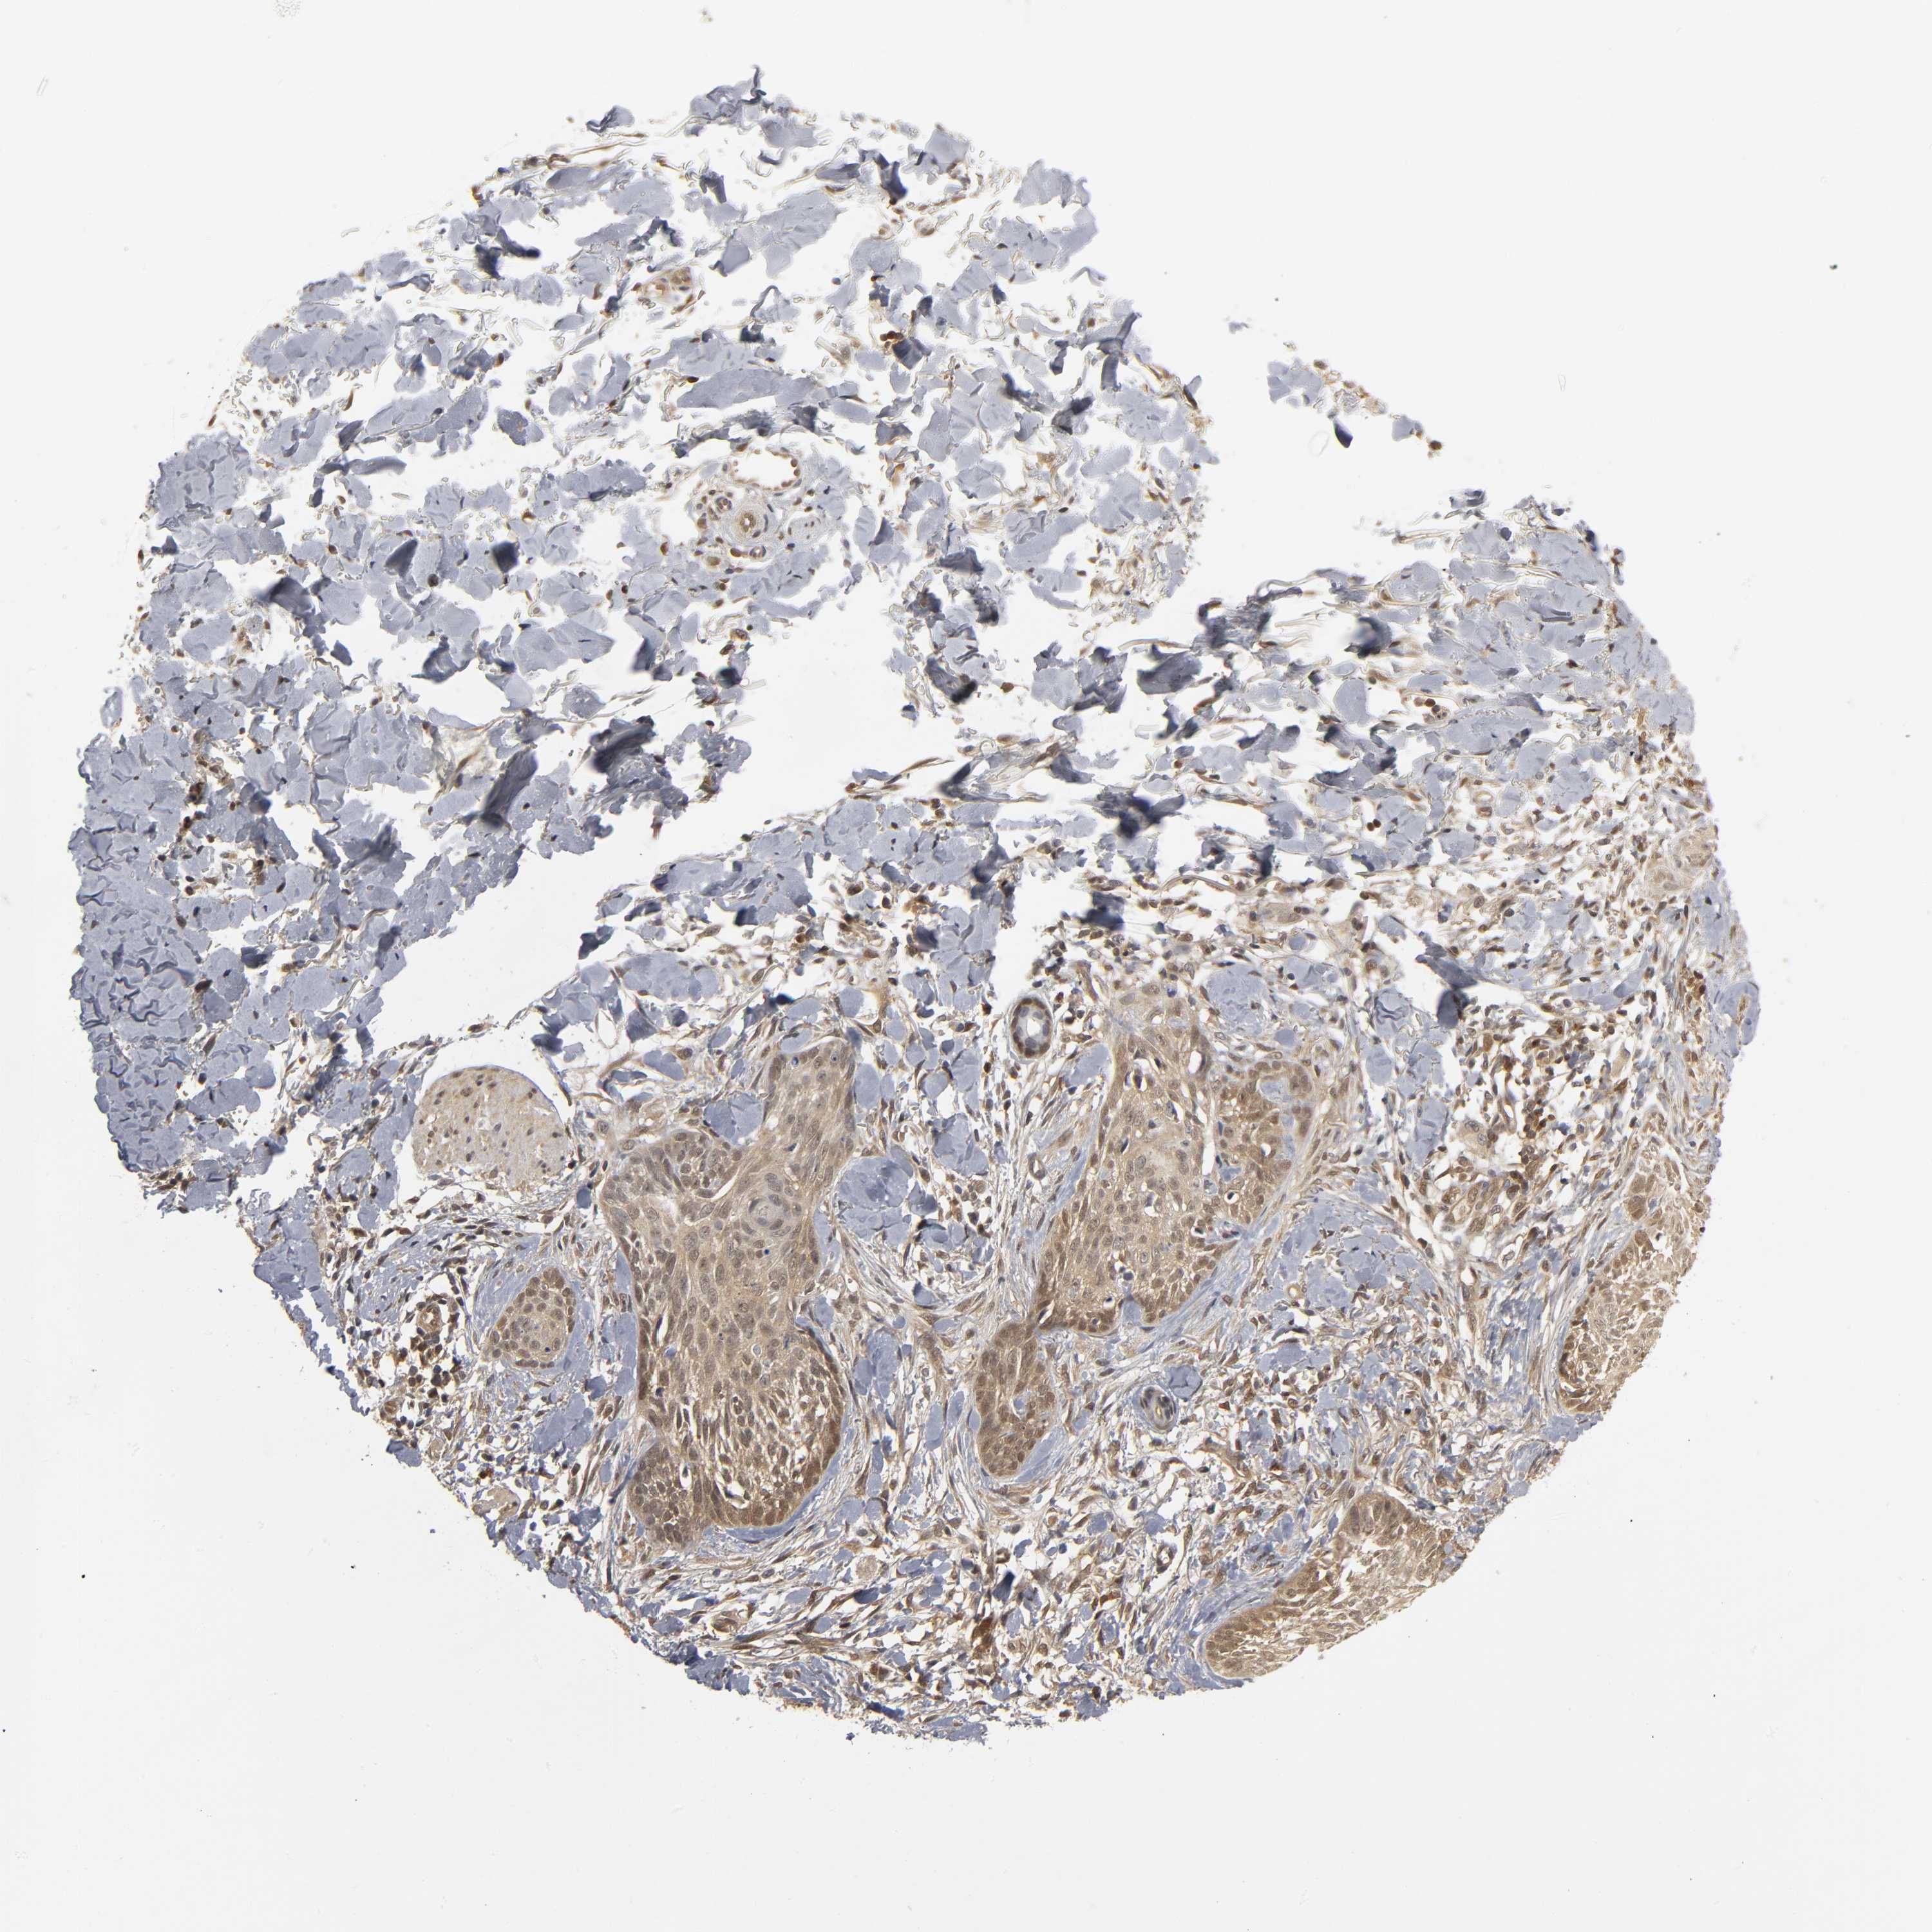

SKIN CANCER - Protein expressioni

A mouse-over function shows sample information and annotation data. Click on an image to view it in a full screen mode. Samples can be filtered based on level of antibody staining by selecting one or several of the following categories: high, medium, low and not detected. The assay and annotation is described here.

Antibody stainingi

Antibody staining in the annotated cell types in the current human tissue is reported as not detected, low, medium, or high, based on conventional immunohistochemistry profiling in selected tissues. This score is based on the combination of the staining intensity and fraction of stained cells.

Each image is clickable and will lead to virtual microscopy that enables deeper exploration of all samples and also displays staining intensity scores, fraction scores and subcellular localization as well as patient and tissue information for each sample.

Antibody HPA004190

Antibody CAB005870

Squamous cell carcinoma, NOS

Basal cell carcinoma